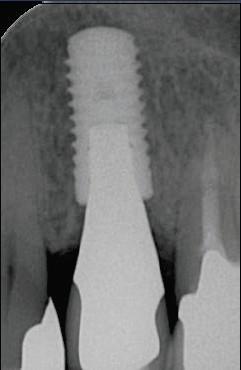

Straumann synOcta — стоит особняком. В этой системе, при типе соединения восьмигранник, реализована оригинальная концепция. Суть её в том, что имплантат и десневая часть абатмента составляют единое целое, что дает значительный выигрыш в долгосрочной перспективе в стабильности костной ткани вокруг шейки имплантата (Рис. 1,2,3). А также внутренний восьмигранник с конусом Морзе (Рис. 4), уступ коронки на имплантате (Рис. 5). Выбор компонентов — самый внушительный среди всех систем в мире. Склад превосходный — все есть. Информационная поддержка — вне конкуренции.Недостатки — система сложная на хирургическом и зуботехническом (требует высокой квалификации) этапах. ДОРОГАЯ.

Рис. 1

Рис. 2

Рис. 3

Рис. 4

Рис. 5